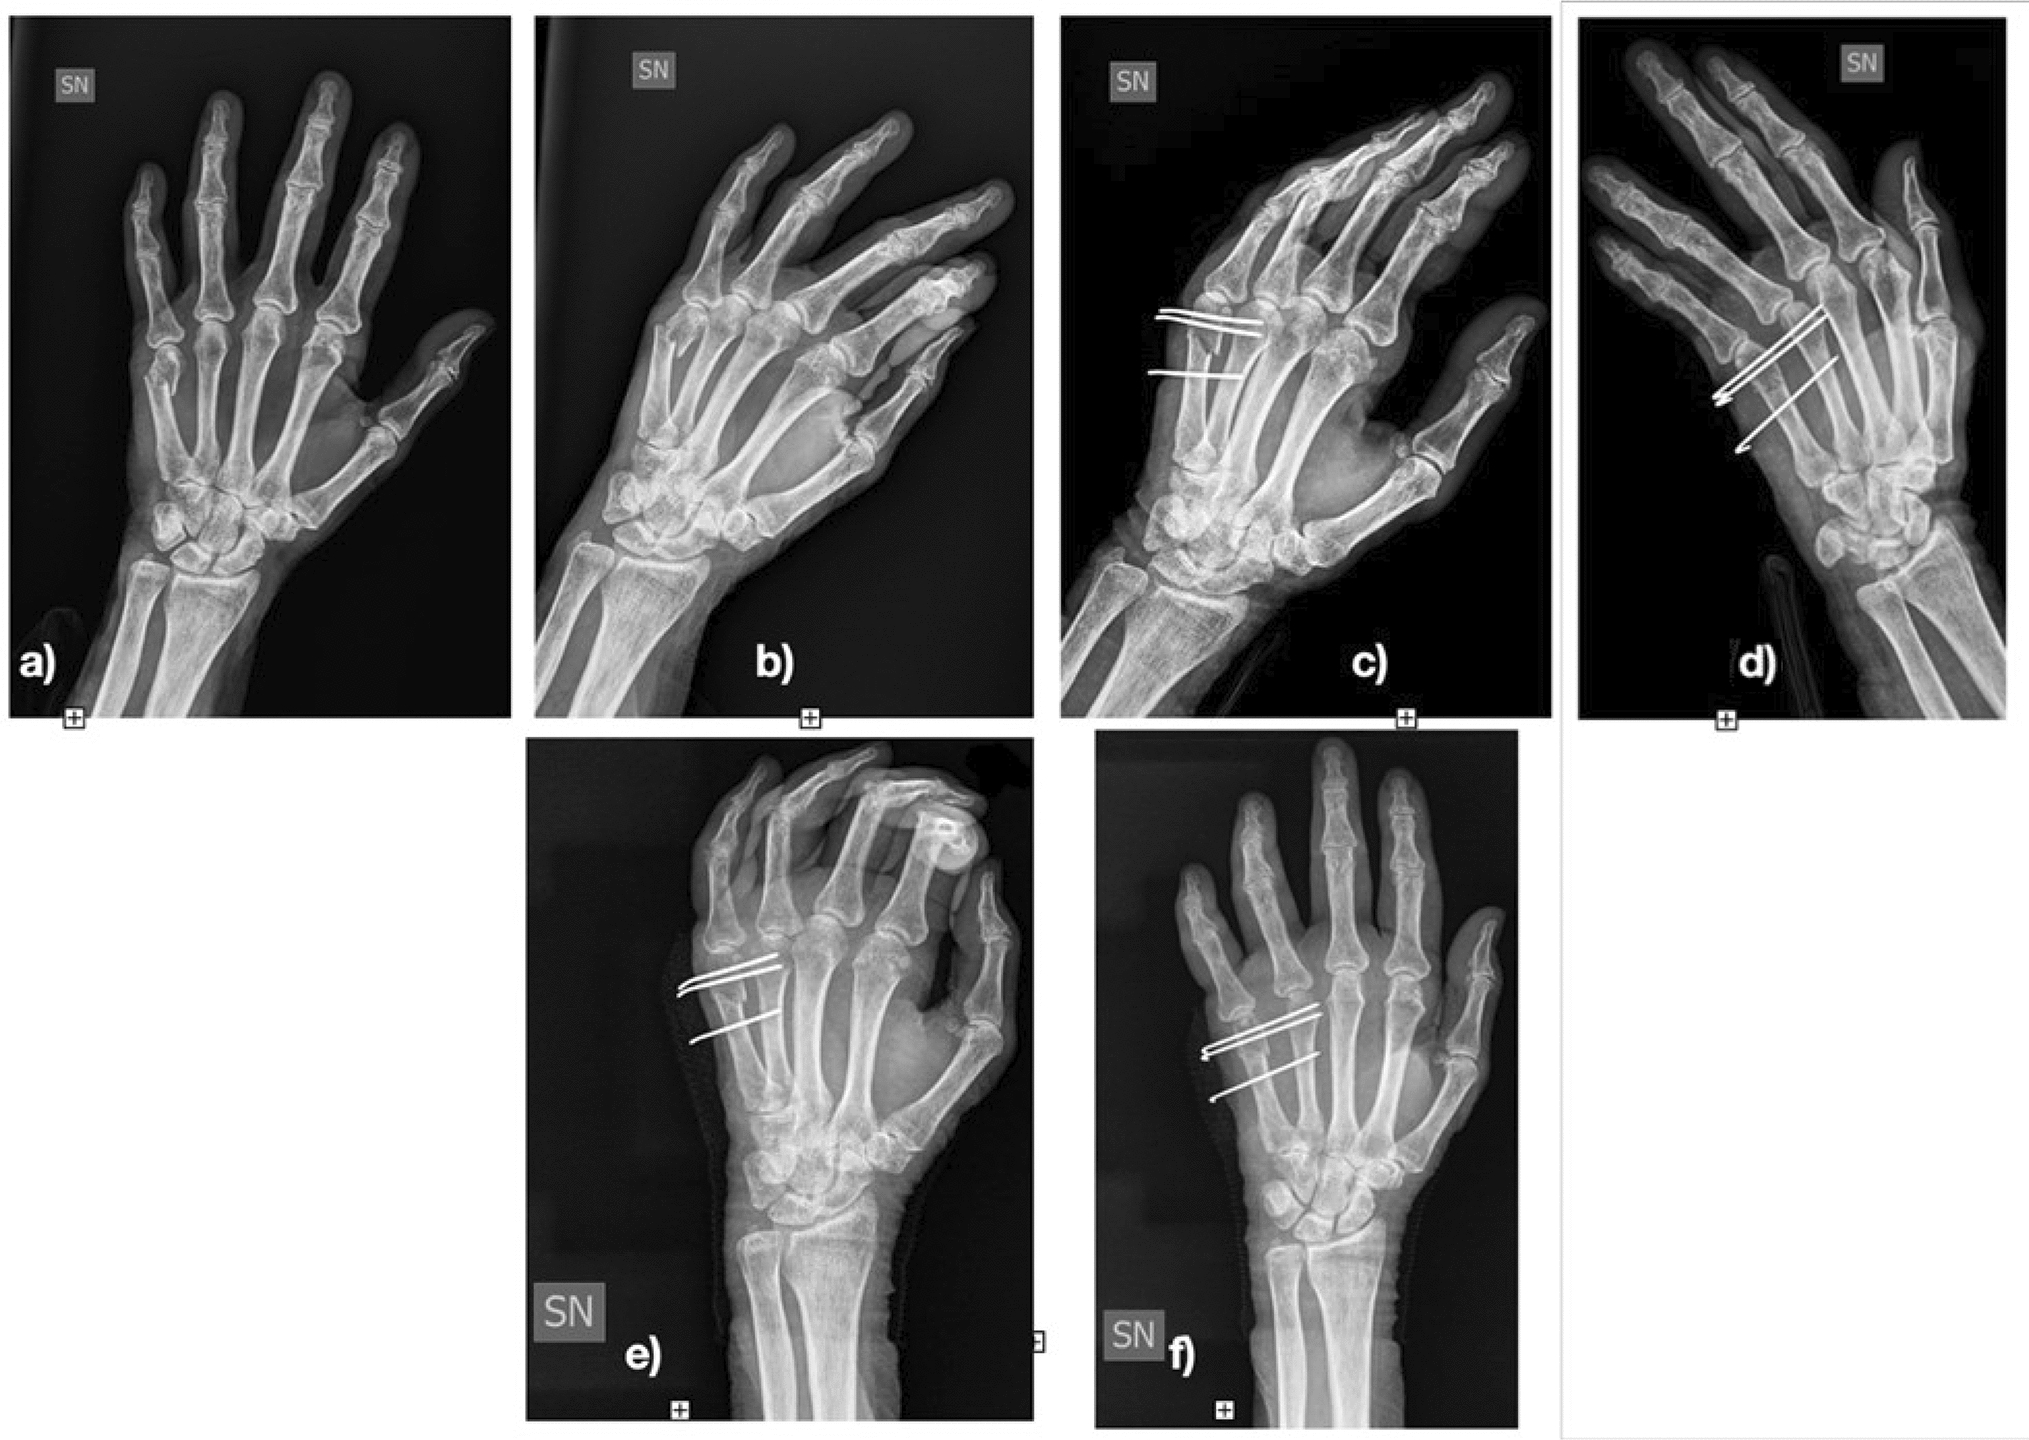

All patients underwent loco-regional anaesthesia. As antibiotic prophylaxis, 2 g of intravenous cefazolin were administered before surgery. Closed reduction of the fracture was performed under image intensification. In some fractures, especially spiral or severely displaced (11 of 56), open reduction was necessary, performing a dorsal mini-incision to reduce the fracture as anatomically as possible. The most important target was to correct the rotational deformity. Fixation was performed with 1 or 2 K-wires 1.2 mm in diameter proximal to the fracture and with 1 or 2 K-wires distal the fracture to avoid displacement in the sagittal plane of the distal portion of bone. The K-wires were advanced through the fractured metacarpal up to the far cortex of the adjacent metacarpal (Figs. 1 and 2).

Fig. 2

Fourth metacarpal spiral fracture. a post-operative radiography; b and c 1-month post-operative radiography; d and e 3-month post-operative radiography